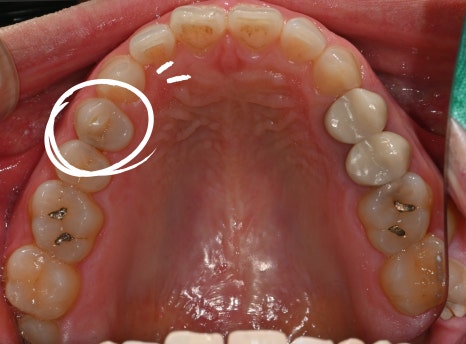

When the patient first visited the clinic

My molar cracked, and when I chew, it gives a sharp, aching pain.

After checking the photos and X-rays taken at the dental clinic,

bacteria had entered through the crack,

and the nerve was already severely damaged.